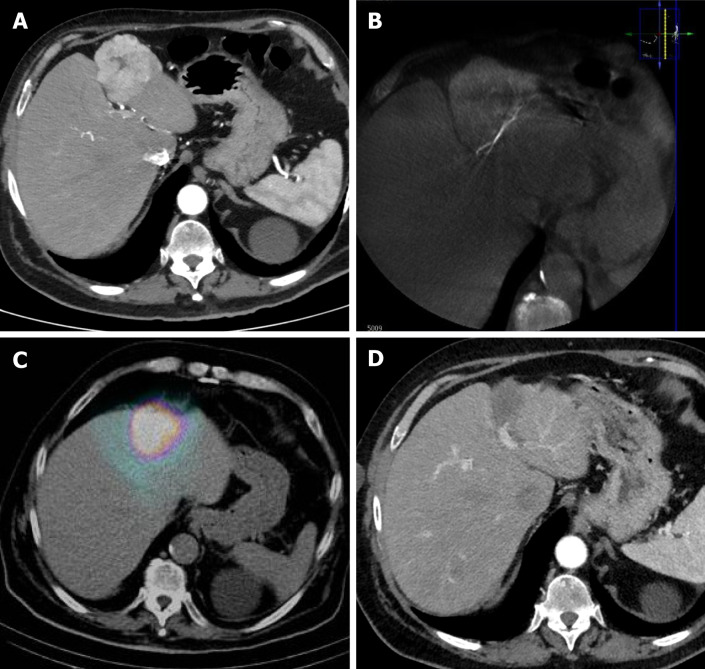

Abstract Image